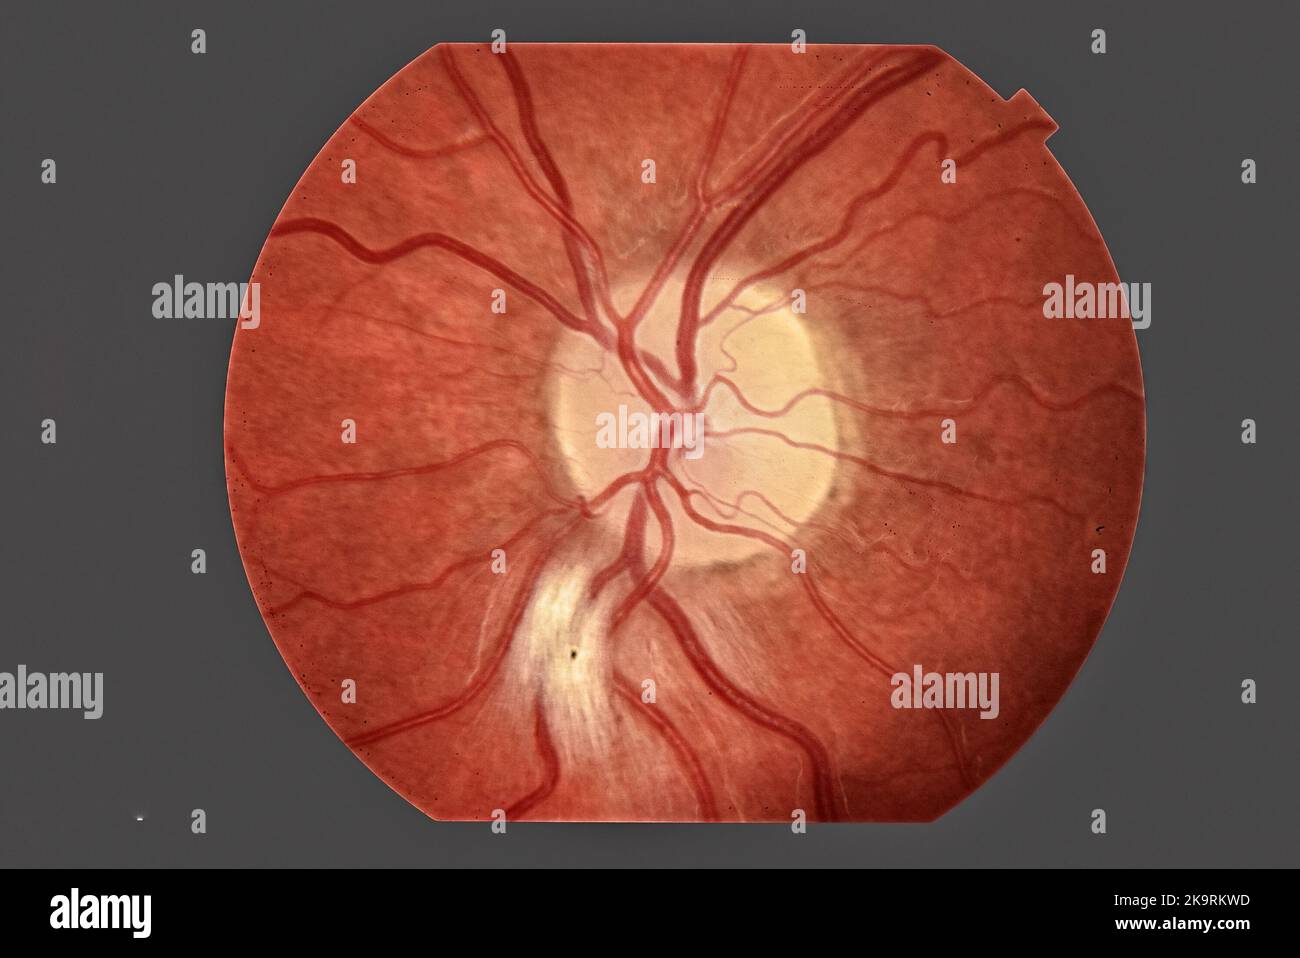

Normal Retina Stock Photohttps://www.alamy.com/image-license-details/?v=1https://www.alamy.com/normal-retina-image352788542.html

Normal Retina Stock Photohttps://www.alamy.com/image-license-details/?v=1https://www.alamy.com/normal-retina-image352788542.htmlRM2BDXWAP–Normal Retina

Photo of human eye anatomy Stock Photohttps://www.alamy.com/image-license-details/?v=1https://www.alamy.com/photo-of-human-eye-anatomy-image487942713.html

Photo of human eye anatomy Stock Photohttps://www.alamy.com/image-license-details/?v=1https://www.alamy.com/photo-of-human-eye-anatomy-image487942713.htmlRF2K9RKWD–Photo of human eye anatomy